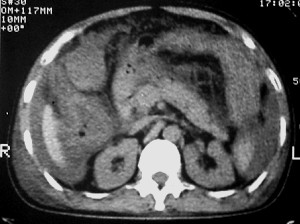

m ,60岁,右上肺ca术后一月。

右侧肺癌术后:肝内可见多个大小不等的低密度结节影。腹腔及双侧胸腔大量积液。考虑:肺癌并胸膜及肝脏转移。

腹水,肝及右肾多发低密度影。考虑转移。

肝及右肾转移瘤,双侧胸水

右肾及肝内多发转移瘤,胸水。

1、右肺癌术后改变。2、双侧胸水、腹水。3、多发性肝囊肿,右侧肾囊肿。